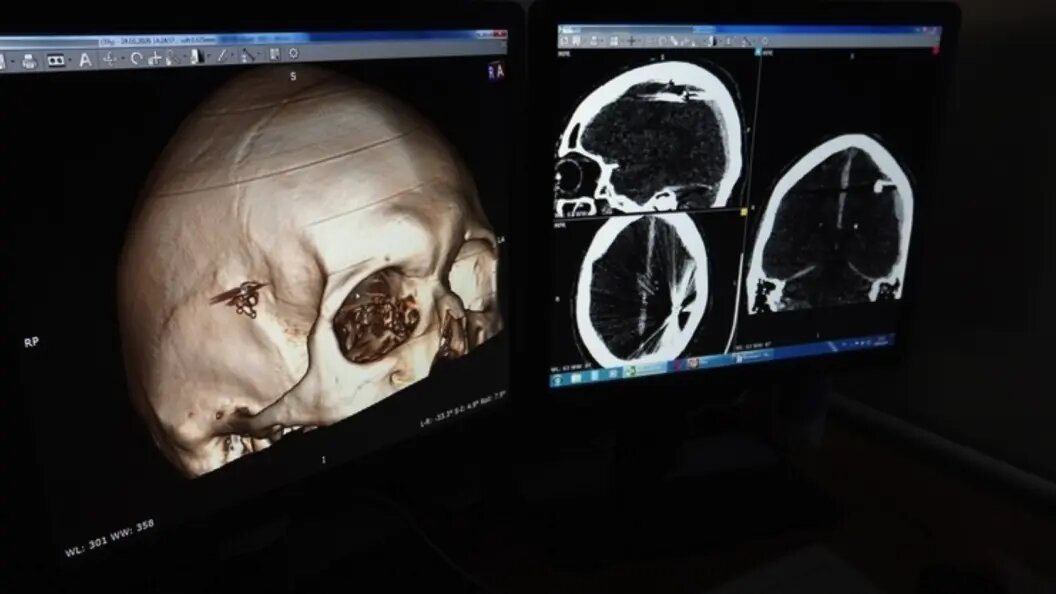

Однако, когда врачи начали обследование, они поняли, что имеют дело с редчайшим случаем. Компьютерная томография показала не просто ушиб, а множественные металлические осколки и пулю в головном мозге пациента.

Как выяснилось, мужчина получил ранение из травматического оружия почти за сутки до госпитализации, но не придал этому значения и к медикам не обращался. В больницу его привезли только после того, как он потерял сознание. К этому моменту пуля, войдя через правую височную область, проделала опасный путь через теменные доли, оставляя за собой кровоизлияния и разрушения тканей.

Нейрохирурги приняли решение об экстренной операции, которая продлилась два с половиной часа. Специалистам предстояло не только извлечь саму пулю, но и удалить костные обломки, осколки металла и гематому, образовавшуюся в раневом канале.